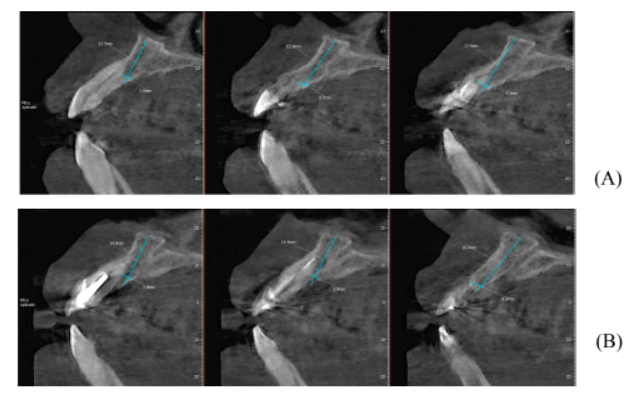

Figuras A,B,C, D e E – Imagens evidenciando grande perda óssea anterior no sentido horizontal, bem como a vestibularização do rebordo anterior, o que impossibilita a instalação dos implantes em um bom posicionamento tridimensional.

Após oito meses, foi realizada outra tomografia computadorizada (TC) na própria clínica escola, onde foram realizadas medidas de altura e espessura evidenciando grande ganho ósseo horizontal. Não ocorreu quaisquer tipo de complicação no pós-operatório tardio (imagens 1-A, 1-B, 1-C, 1-D).